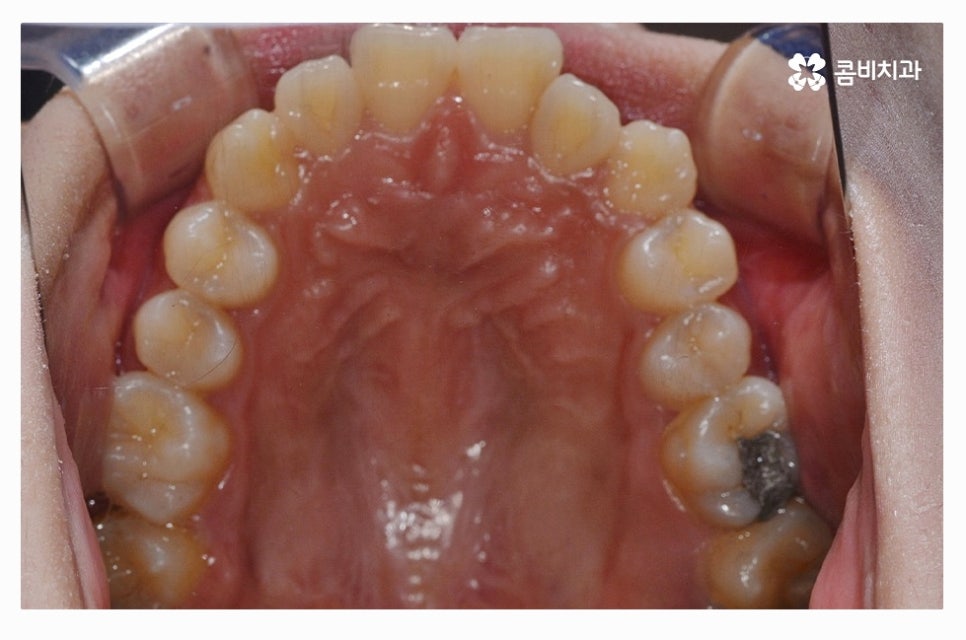

덧니는 치아 사이에 음식물이 끼기 쉽고 치석이 쌓여서

충치 및 잇몸질환이 발생할 수 있으며 덧니로 인한 부정교합이나

턱관절 장애가 발생하는 경우도 있기 때문에 덧니의 정도에

따라서 꼭 덧니교정을 하는 것이 이로운 분들이 있는데요.

덧니교정은 개인차가 크고 비교적 심하지 않은 덧니부터

부정교합이 심한 경우까지 다양하기 때문에

덧니교정을 고민 중이라면 구강 상태를 정밀 진단하고

자신에게 적합한 치료 계획과 교정 장치의 선택,

치료 기간 및 사후관리까지 꼼꼼하게 알아보신 후 결정하실 필요가 있어요.